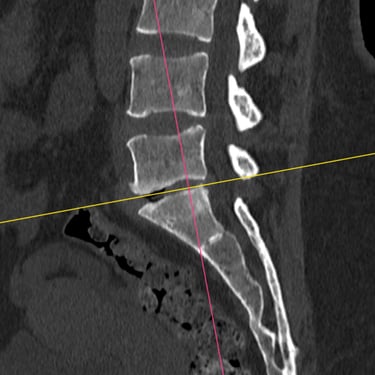

Manejo quirúrgico de la hernia lumbar con inestabilidad: enfoque moderno con FTP y TLIF

La hernia lumbar con inestabilidad vertebral es una patología frecuente que causa dolor lumbar persistente, ciática y limitación funcional, afectando la calidad de vida del paciente. Cuando el tratamiento conservador no logra resultados adecuados, la cirugía se convierte en la mejor opción terapéutica. La fijación transpedicular con tornillos (FTP) junto con la técnica TLIF (Transforaminal Lumbar Interbody Fusion) permite estabilizar la columna, descomprimir las estructuras nerviosas y lograr una adecuada fusión ósea. Este abordaje, especialmente mediante técnicas mínimamente invasivas (MISS), ofrece múltiples beneficios, como menor daño muscular, menor dolor postoperatorio y recuperación más rápida, facilitando el retorno temprano a las actividades cotidianas con mejores resultados clínicos.